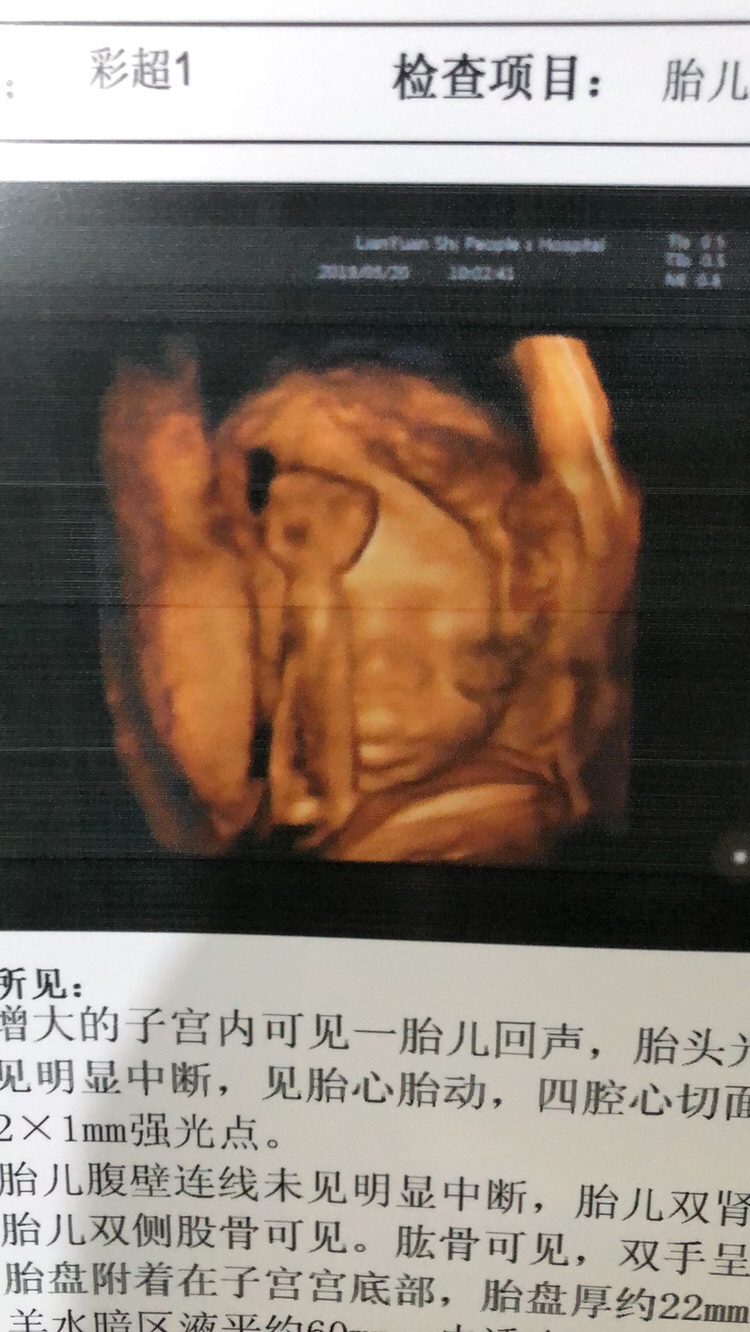

孕29周+1天

多可爱,小手也握拳